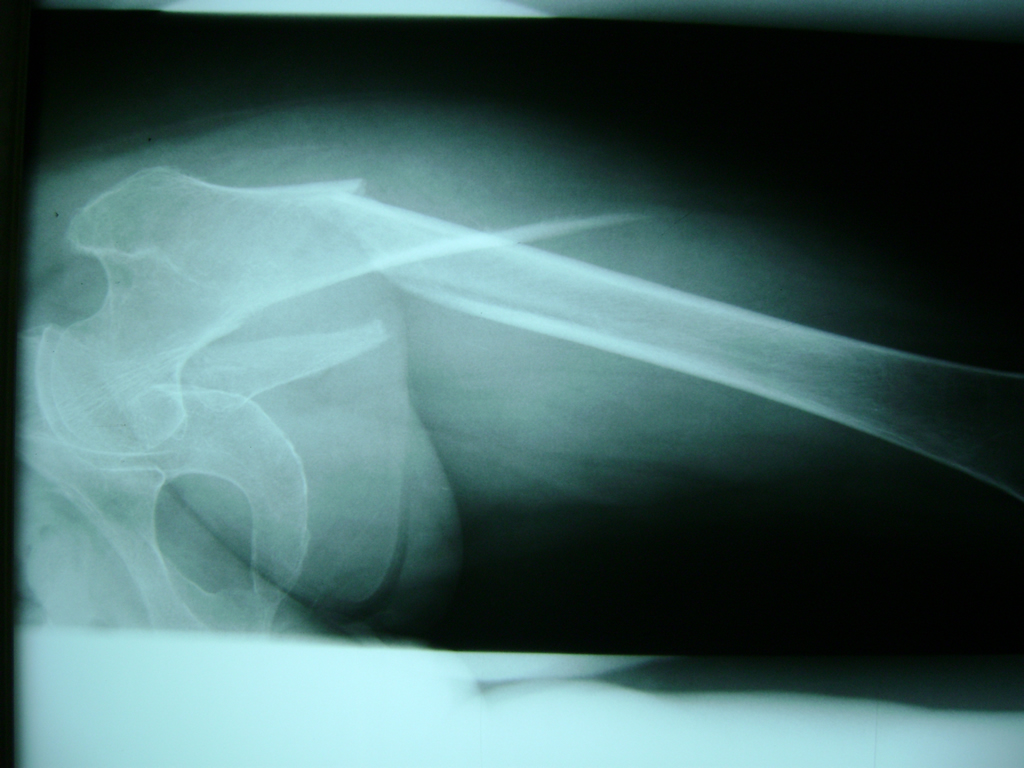

Fémur - Cadera

La cirugía de fractura de cadera se realiza para reparar una ruptura en la parte superior del hueso del muslo. Este hueso se denomina fémur.

Es parte de la articulación coxofemoral. Si una fractura de cadera no recibe tratamiento, es posible que deba permanecer en una silla o en la cama.